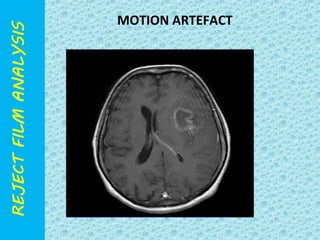

MOTION ARTEFACT